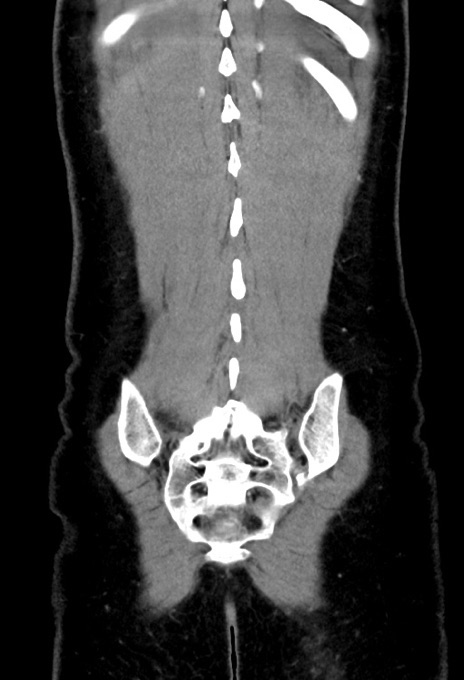

横断像

【症例】20歳代女性

【主訴】嘔吐、下腹部痛

【現病歴】昨日夕食後に嘔吐し下腹部痛が出現。本日になっても嘔吐持続し改善しないため来院。

【身体所見】意識清明、BT 37.2℃、BP 108/67mmHg、腹部:平坦、やや硬、下腹部正中から右にかけて圧痛あり、反跳痛軽度あり、tapping pain(+)。

【データ】WBC 13600、CRP 14.94